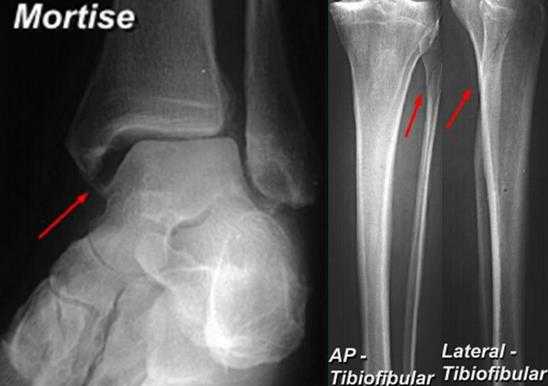

Помимо тщательного сбора анамнеза, осмотра и функциональных тестов, важную роль в диагностике повреждений межберцового синдесмоза играют инструментальные методы. В первую очередь выполняются рентгенограммы в прямой и боковой проекции голени на протяжении, для исключения высоких переломов лодыжек.

Вторым важным моментом является выполнение снимков с выведением межберцового «паза» (проекция Mortise, 15-20° внутренней ротации голени).

Её информативность значительно возрастает при выполнении рентгенограмм с нагрузкой и одновременно обеих нижних конечностей. Помимо «пазовой» рентгенограммы в диагностически неоднозначных случаях выполняют стресс-рентгенограммы с наружной ротацией.

Признаками, указывающими на разрыв межберцового синдесмоза служат:

-сниженное взаимное перекрытие берцовых костей, в норме >6 мм на передней и >1 мм на «пазовой» рентгенограммах.

-увеличенное медиальное чистое пространство >4 мм.

-увеличенное большеберцово-малоберцовой чистое пространство, в норме